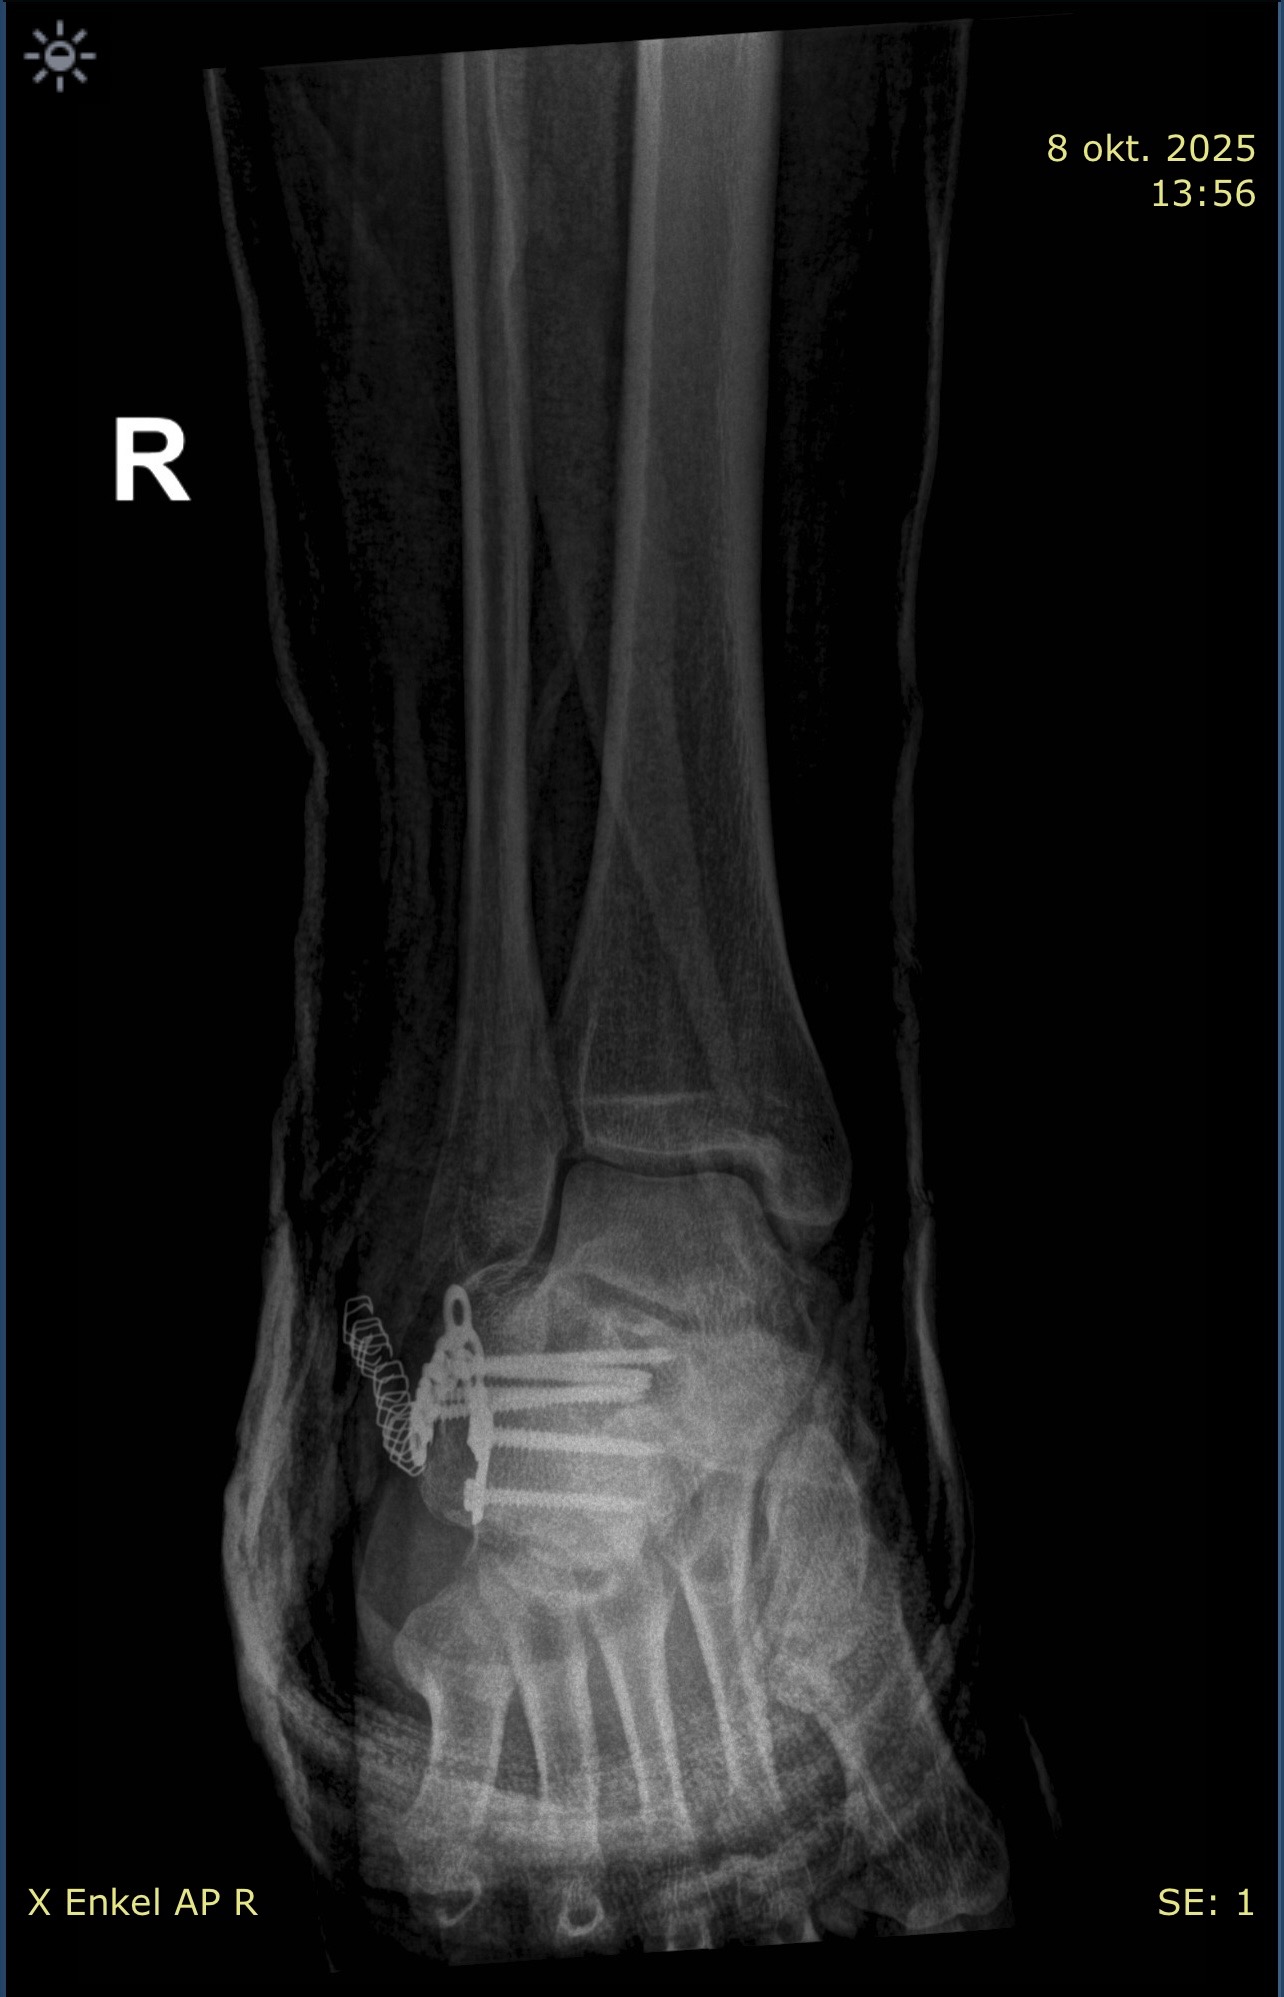

• Een verbrijzelde hiel (waar ik intussen aan geopereerd ben)